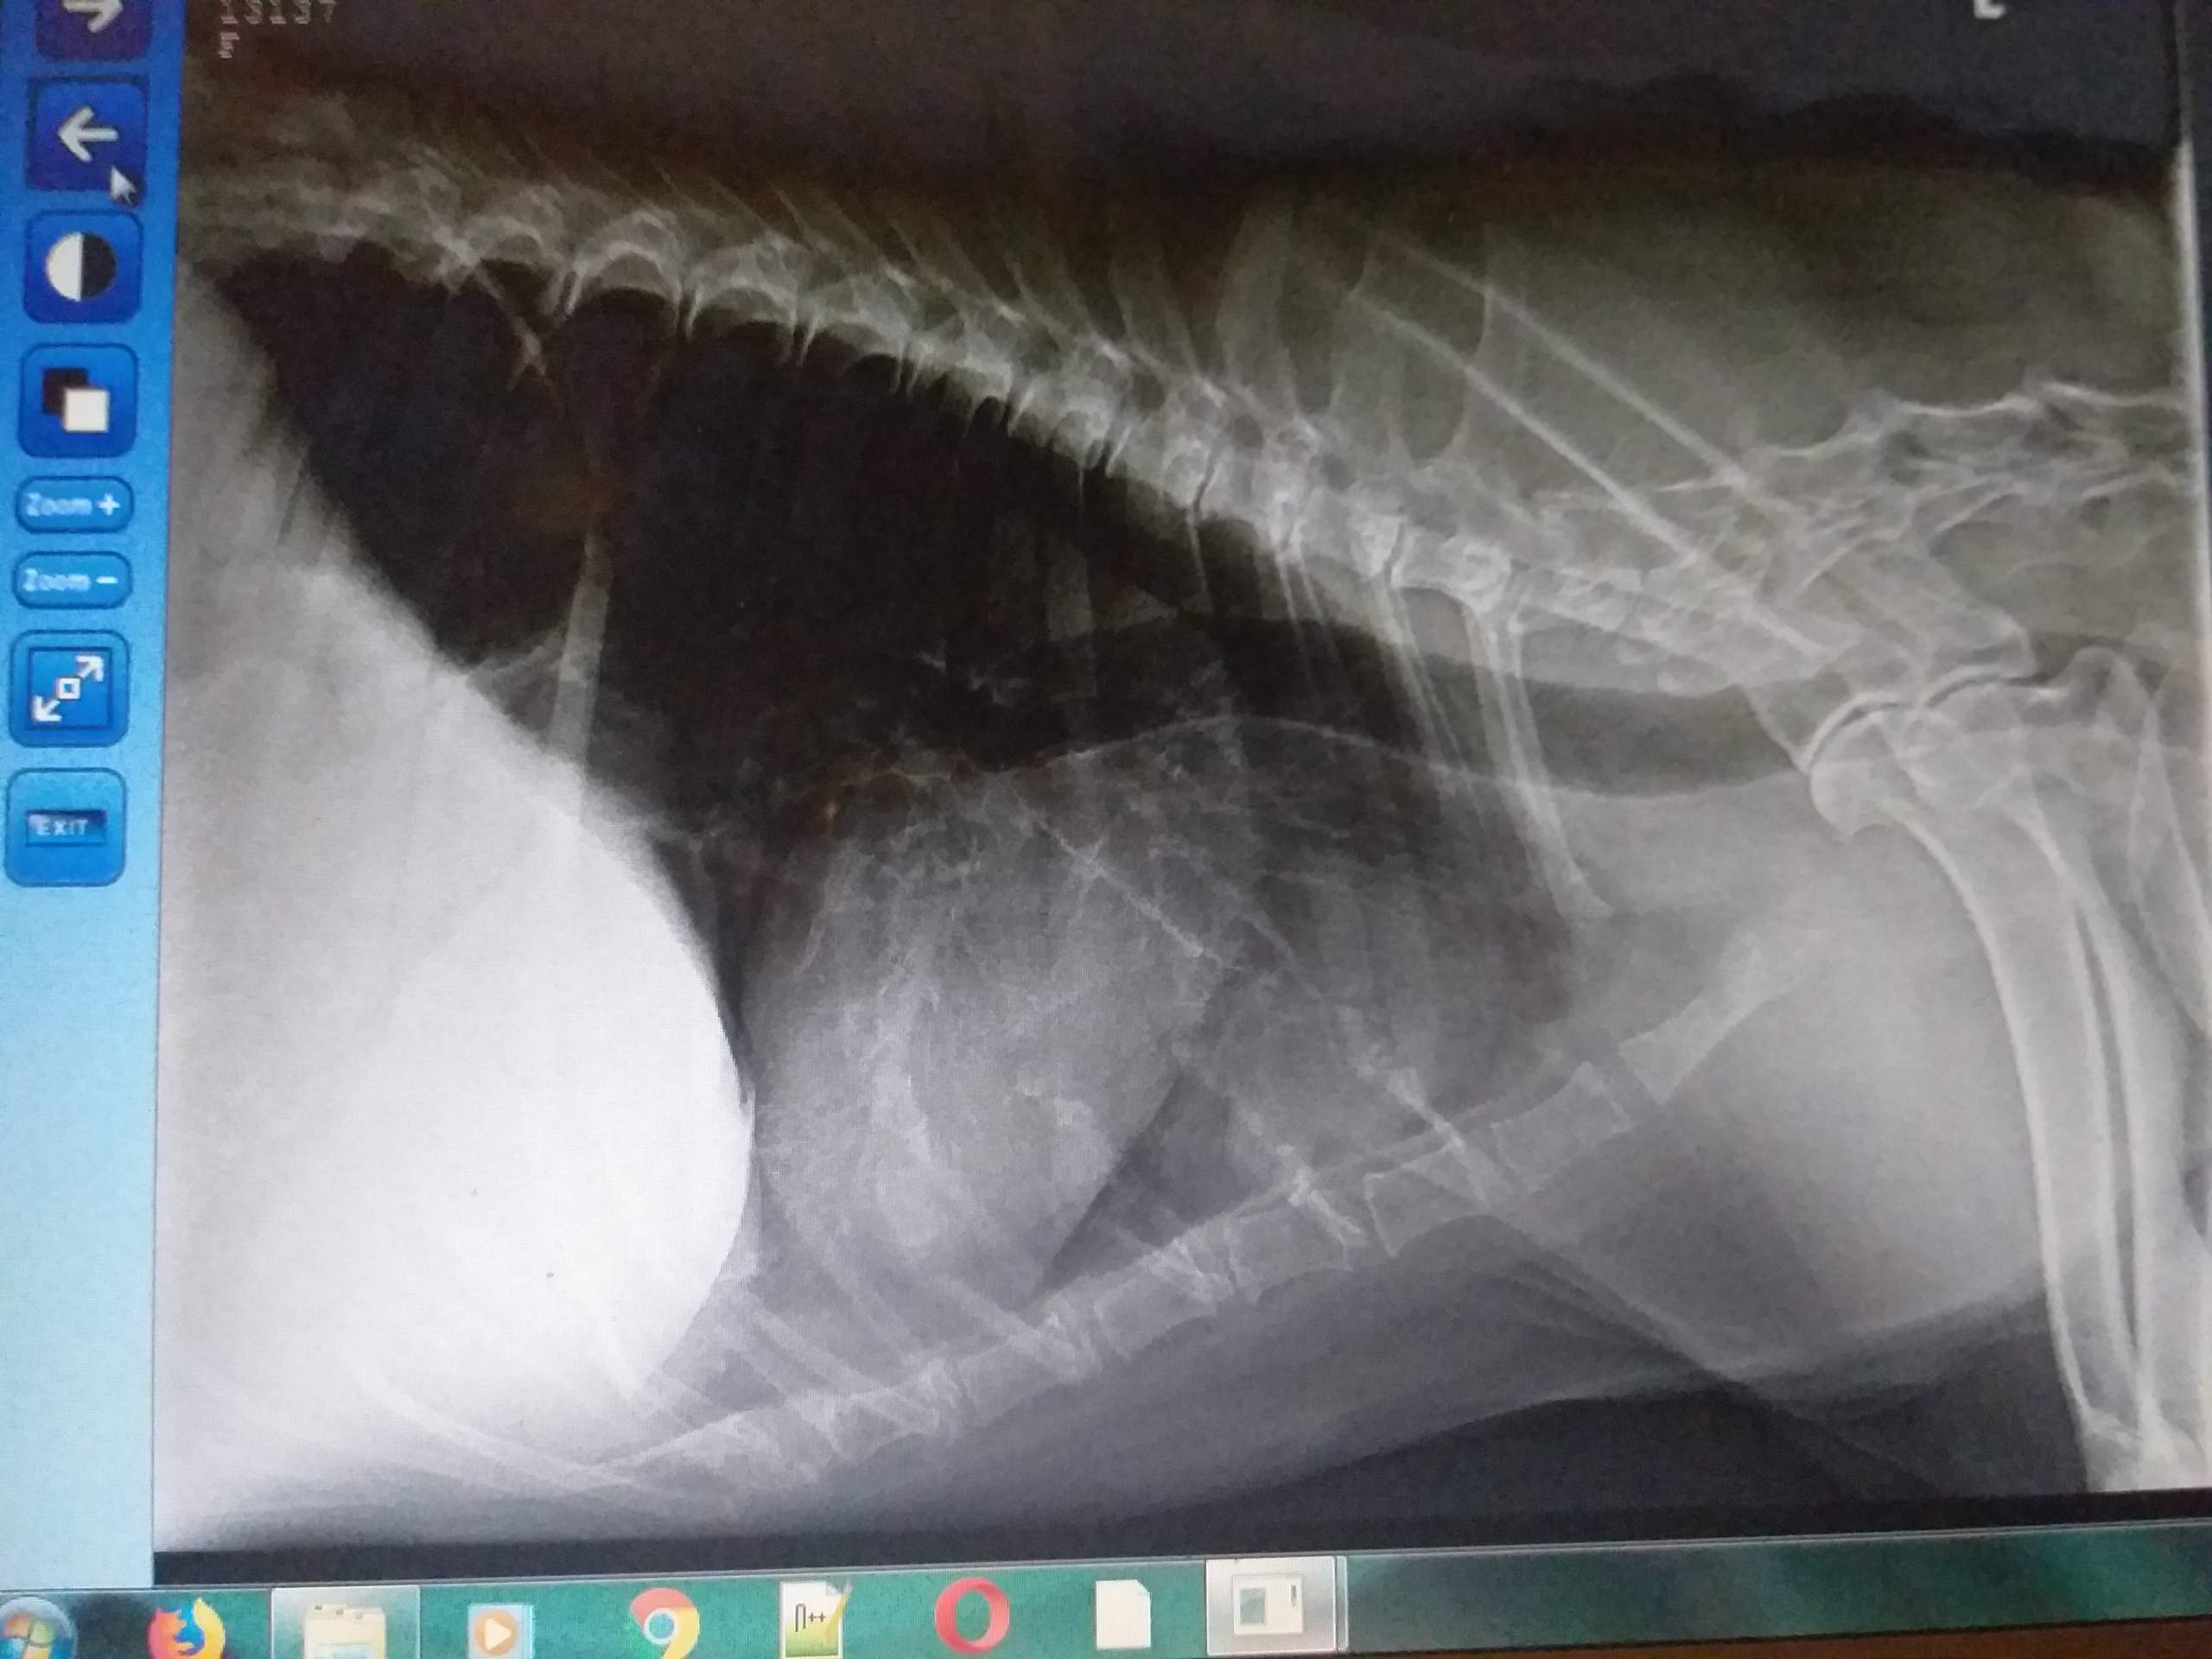

SechsKiloTumor Kann dieser Hund noch gerettet werden?

Dieser Hund hatte einen 6 kg schweren Tumor... Eine Tierschutzverein